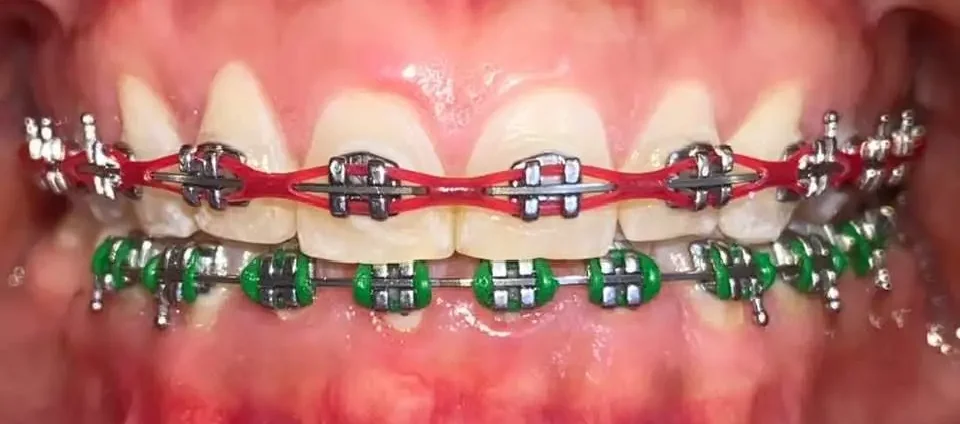

Corregimos la posición de los dientes y la mordida para lograr una sonrisa armónica y una función dental óptima. Este tratamiento, realizado por un especialista en Ortodoncia, transformara tu sonrisa y evitara problemas futuros en tu salud bucal.

Agenda tu citaOrtodoncia(Brackets)